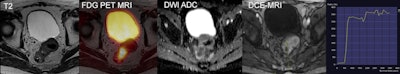

Novel concepts toward intrinsic compensation of involuntary patient motion are being worked on, a prerequisite for subsequent partial volume correction (figure 1), or anatomic-guided image reconstruction. The better the alignment of the two sets of imaging information, the more valuable the clinical information of an integrated PET/MRI examination (figure 2). Also, the palette of PET/MRI scenarios is being expanded through the adoption of the concept of an automated image-derived input function as a prerequisite for parametric imaging, as well as through the adoption of novel radiotracers, such as gallium-68 prostate-specific membrane antigen (Ga-68 PSMA) for multiparametric PET/MR imaging of prostate cancer.

Figure 2: Combined F-18 FDG PET/MRI of a primary upper rectal cancer demonstrates a metabolically active tumor with restricted diffusion and type II enhancement curve. Images courtesy of King's College London.